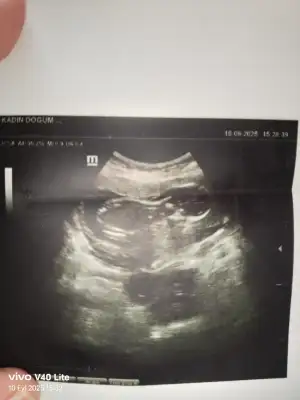

Kızlar 13 haftalık doktor kız gibi sürüyor dedi. Ama pay bıraktı sizce kız mı